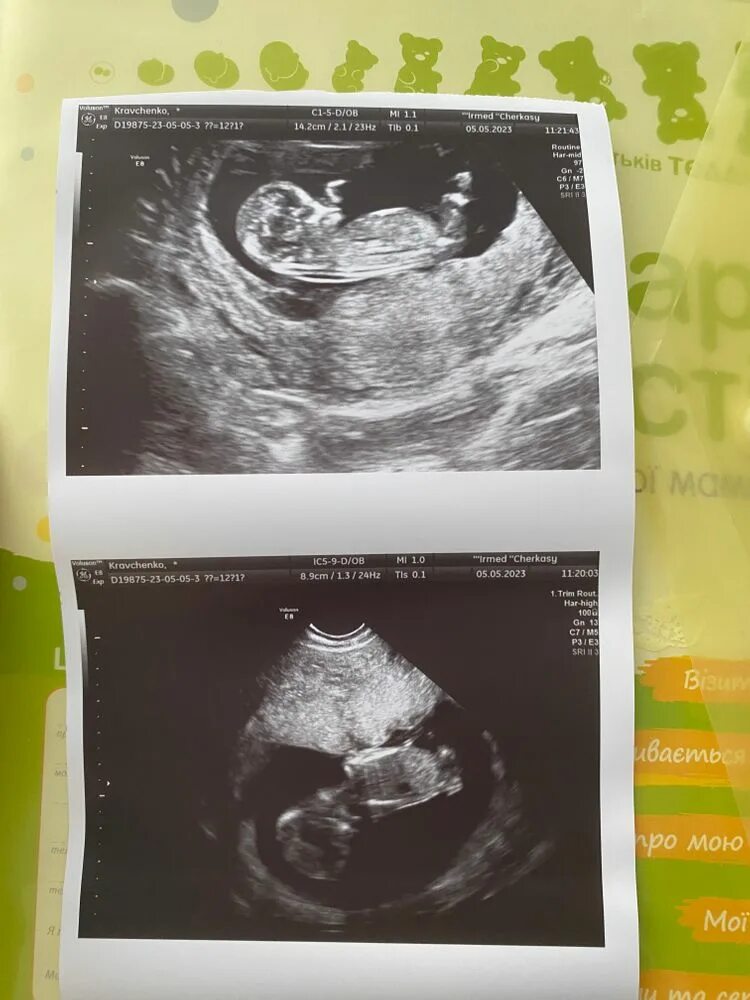

Сколько по времени длится скрининг 1